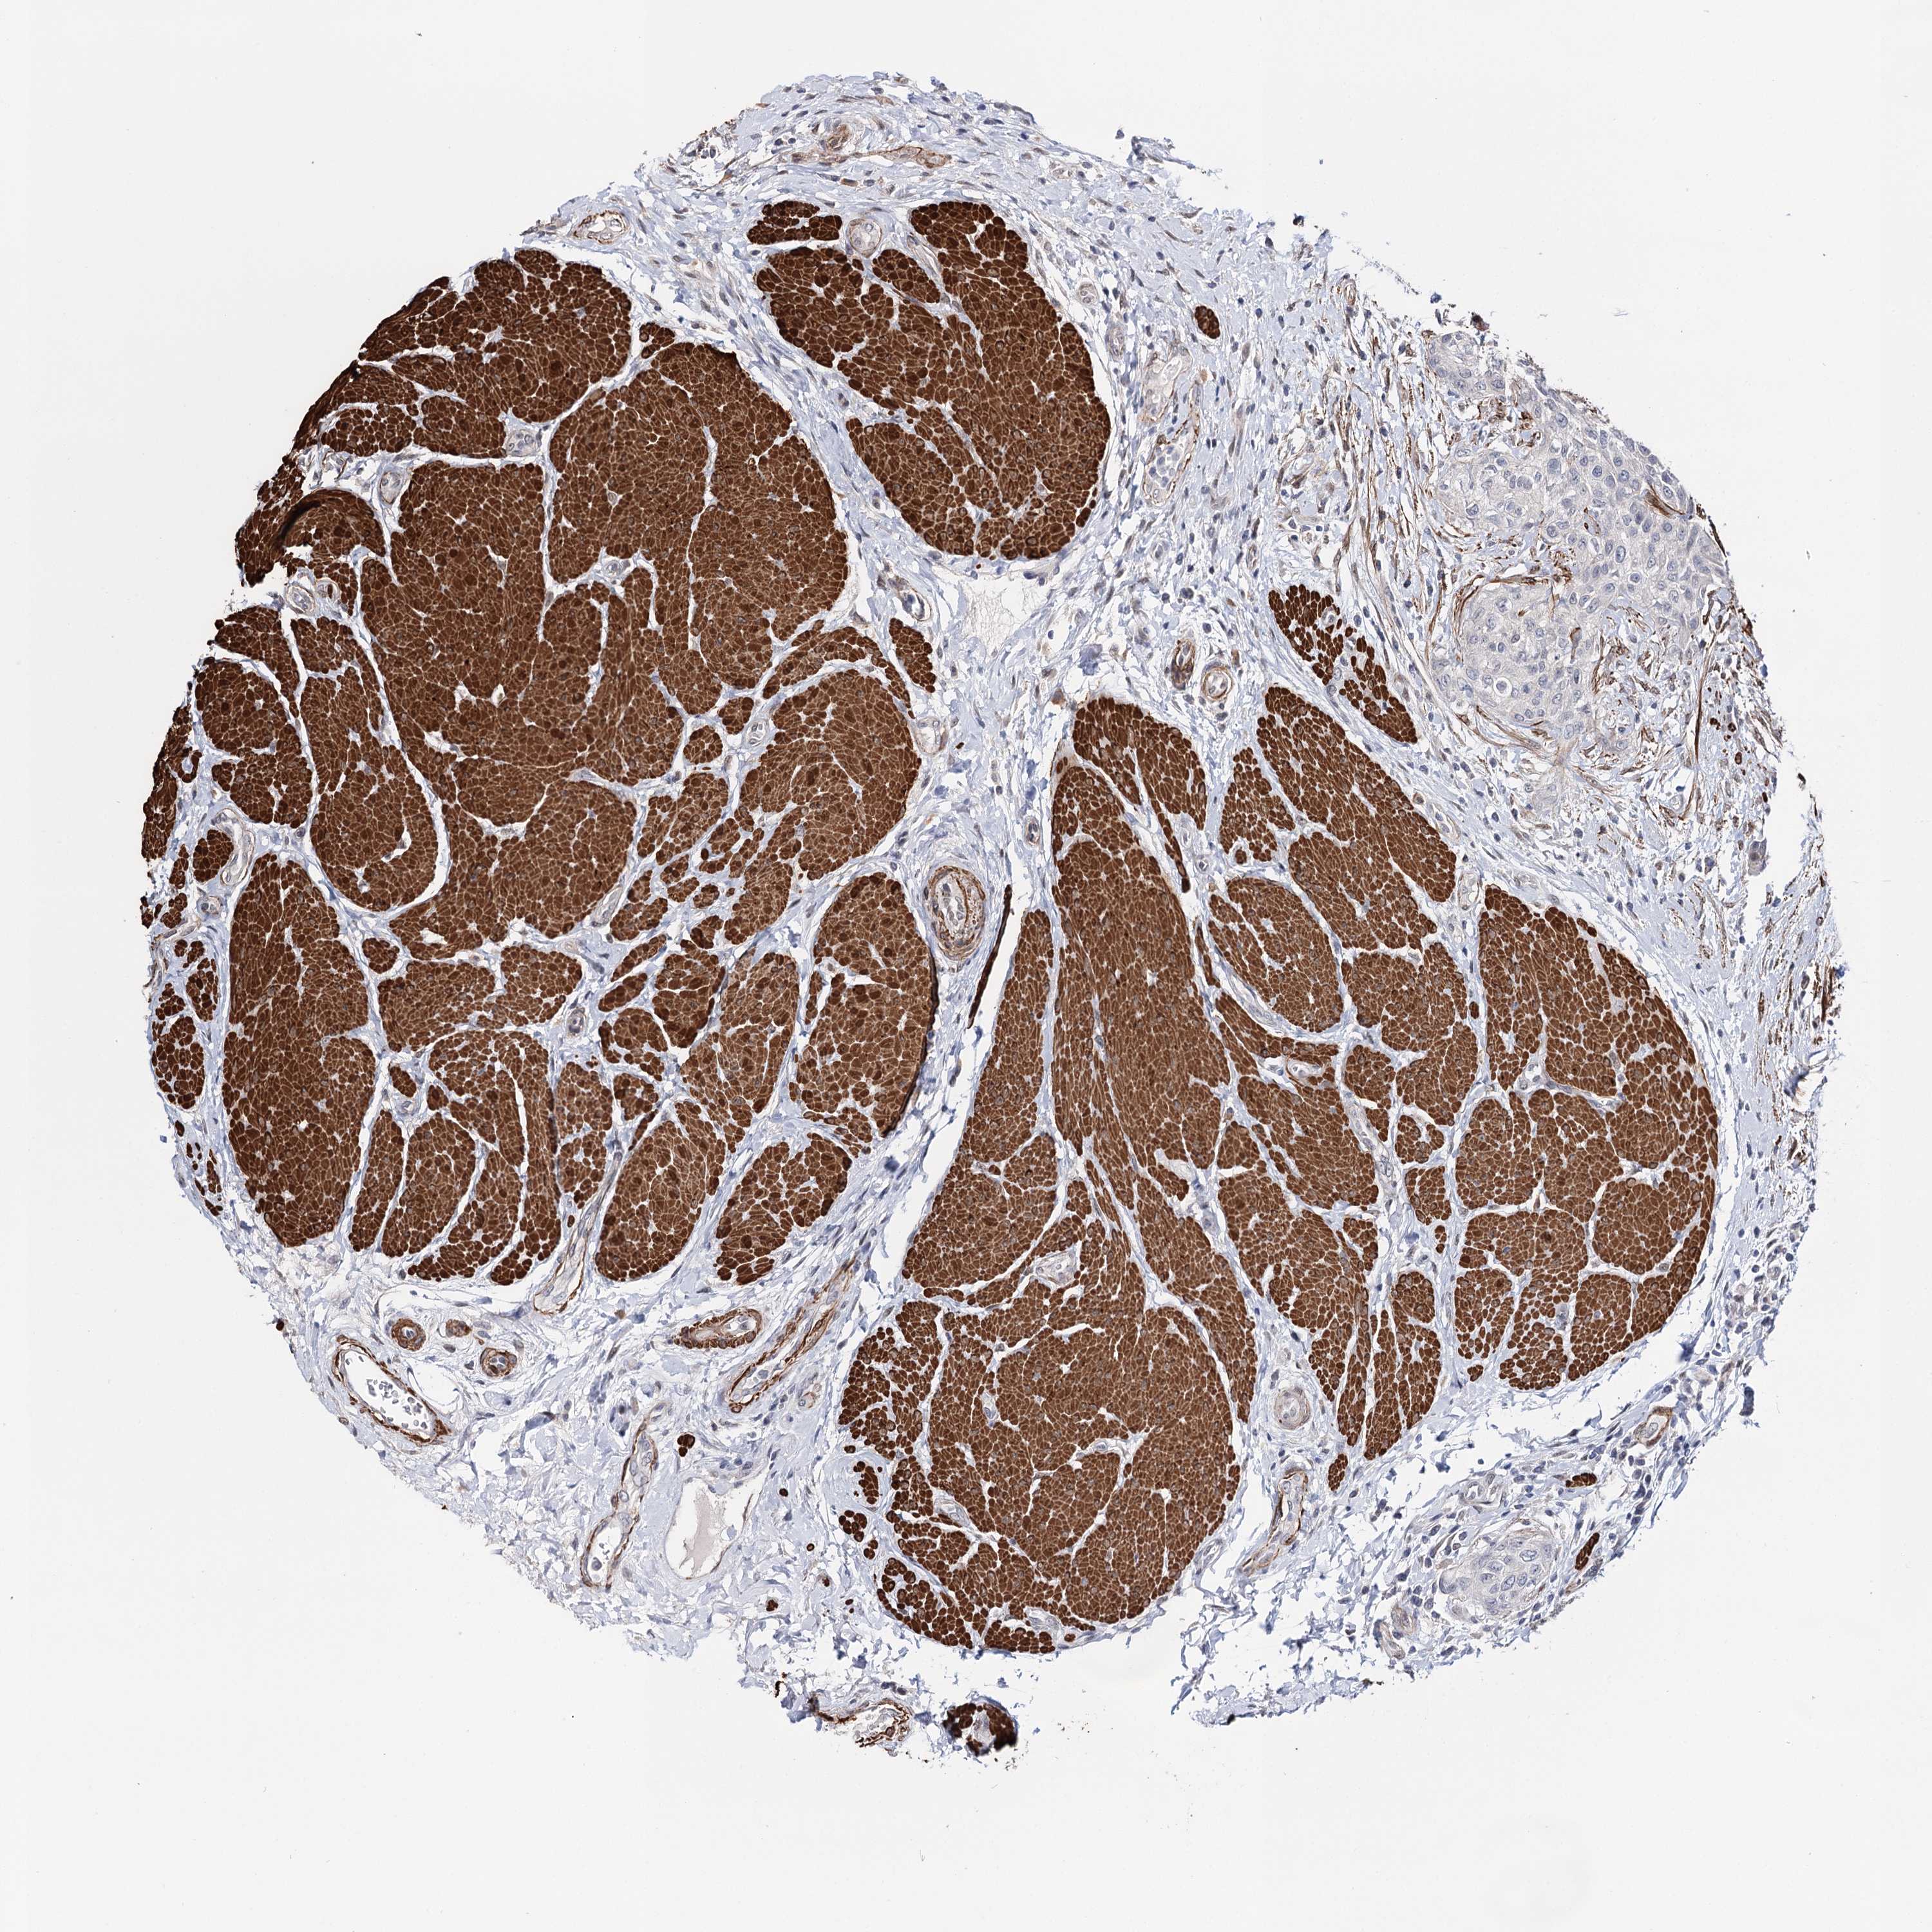

UROTHELIAL CANCER - Protein expressioni

A mouse-over function shows sample information and annotation data. Click on an image to view it in a full screen mode. Samples can be filtered based on level of antibody staining by selecting one or several of the following categories: high, medium, low and not detected. The assay and annotation is described here.

Note that samples used for immunohistochemistry by the Human Protein Atlas do not correspond to samples in the TCGA dataset.

Antibody stainingi

Antibody staining in the annotated cell types in the current human tissue is reported as not detected, low, medium, or high, based on conventional immunohistochemistry profiling in selected tissues. This score is based on the combination of the staining intensity and fraction of stained cells.

Each image is clickable and will lead to virtual microscopy that enables deeper exploration of all samples and also displays staining intensity scores, fraction scores and subcellular localization as well as patient and tissue information for each sample.

Antibody HPA037786

Antibody HPA038034

Antibody HPA038867

Antibody HPA038868

Staining

High

Medium

Low

Not detected

Intensity

Strong

Moderate

Weak

Negative

Quantity

>75%

75%-25%

<25%

None

Location

Nuclear

Cytoplasmic/membranous

Cytoplasmic/membranous,nuclear

Urothelial carcinoma, High grade

Urothelial carcinoma, Low grade

Urothelial carcinoma, NOS